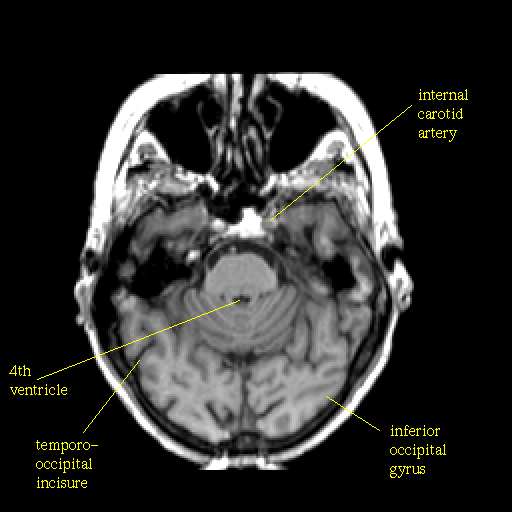

T1-weighted structural MR: Slice 16

Slice 16